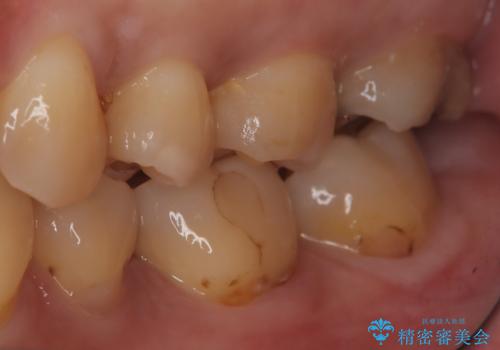

- 主訴:左上の銀の詰め物、笑うと見えそうで気になるので白くしたい。

保険適応のメタルインレーが入っていたため、適合性・審美性の良いセラミックインレーでのやり替えとなりました。

保険適用のメタルインレーを除去したところ、歯質との境目部分にカリエスを認めたため、カリエス除去しCR裏層の後、セラミックインレーを形成しました。